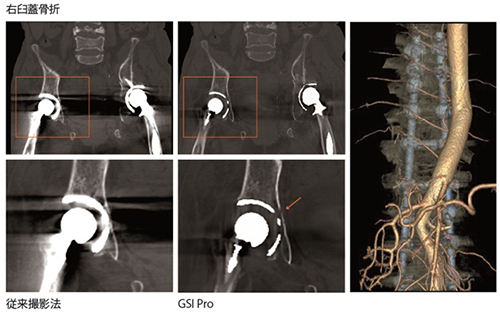

クリニカルアウトカム<4> 留置された金属デバイスに合わせたフォローアップ *

今後増え続けるさまざまな金属インプラントの術後の アーチファクトを低減します。